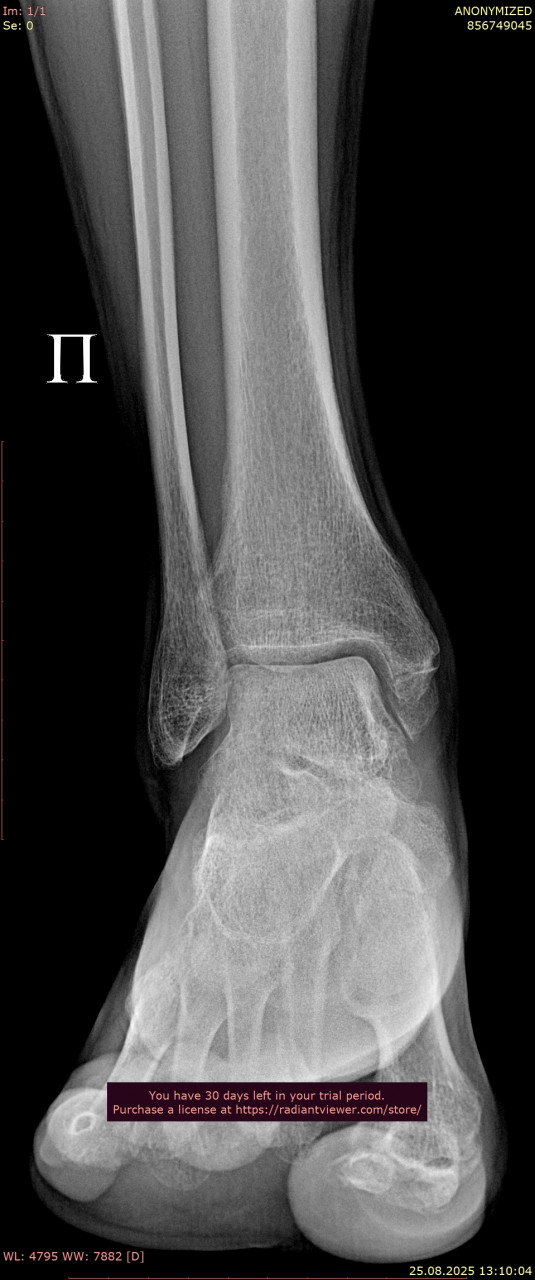

Посмотрите, пожалуйста, снимки стопы и лодыжки от 25.08.2025, перелом был 9 недель назад, 23.08.2025, прикрепляю только прямую проекцию так как лимит сайта 3 файла. Зажили ли переломы, можно ли начинать ходить без дополнительной опоры? Мне 38, мужчина, рост 179, вес 64. Мне говорили что на снимках есть артроз суставов. Подскажите, пожалуйста, насколько он выражен, опасно ли это? Может нужны процедуры, лекарства?

Здравствуйте. На представленных снимках признаки консолидации перелома есть, но судить окончательно о степени сращения и возможности полной нагрузки можно только по всем проекциям. Остальные снимки можно прикрепить ниже при ответе для более точной оценки.

По вашим новым снимкам от 28.07 и контрольным от 25.08 признаков несращения или смещения нет т.к переломы в области стопы и голеностопного сустава консолидируются, костная мозоль выражена, контуры ровные. То есть прочность костей уже достаточна, чтобы постепенно начинать ходьбу без ходунков. То, что вы пока ставите ногу без активного сгибания пальцев, допустимо и так обычно и бывает на этапе ранней нагрузки. Постепенно с помощью ЛФК и разминки подвижность пальцев и стопы восстановится. Перегрузки голеностопа при аккуратной ходьбе на полной стопе сейчас не будет, наоборот  умеренная нагрузка нужна для правильного ремоделирования костной ткани.